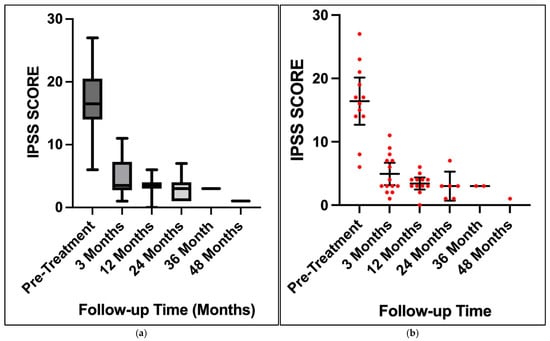

Background/Objectives: Lichen sclerosus is a chronic lymphocyte-mediated inflammatory disorder with a predilection for the anogenital region. It is a common cause of urethral stricture disease in males. The gold standard treatment is considered to be surgical reconstruction; however, there are many patients who are not suitable or not willing to undergo surgery. Cutaneous lichen sclerosus restricted to the foreskin, prepuce or glans is often response to topical corticosteroids; however, the use of intraurethral corticosteroids for urethral involvement has limited research. Methods: We conducted a retrospective cohort study on 18 patients with histologically confirmed lichen sclerosus and associated urethral stricture disease. They were treated with clean intermittent self catheterisation using a hydrophilic catheter coated with 0.05% betamethasone ointment. International Prostate Symptom Score with Quality of Life scores were measured prior to treatment and at follow-up intervals. Results: There was significant improvement in International Prostate Symptom Score and Quality of Life scores at 3 months, 12 months and 24 months, with only 1 patient ceasing treatment due to intolerance. One patient required a single repeat endoscopic dilatation following a period of non-compliance with treatment. Conclusions: Intraurethral corticosteroids with clean-intermittent self-catheterisation is effective and well tolerated for treating lichen sclerosus-associated urethral stricture disease in the short to intermediate term for patients not willing to undergo urethroplasty.

Figure 1